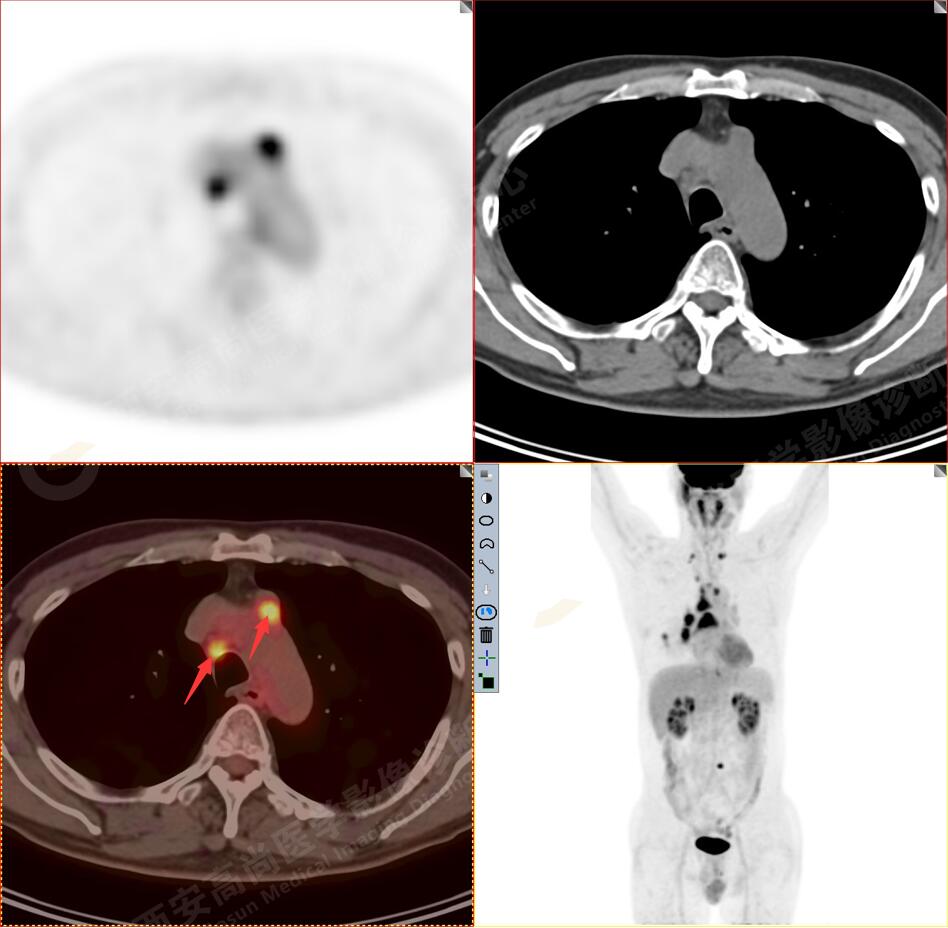

2.以下為全身多發(fā)轉(zhuǎn)移灶

2.雙肺多發(fā)高密度小結(jié)節(jié)灶(最大徑約0.7cm),部分較大結(jié)節(jié)呈FDG代謝略增高,均考慮為轉(zhuǎn)移性病變。

3.右側(cè)肺門、縱隔(1L、1R、3A、4、6、7組)及雙側(cè)鎖骨上多發(fā)腫大淋巴結(jié),呈不同程度FDG代謝異常增高,考慮為淋巴結(jié)轉(zhuǎn)移。